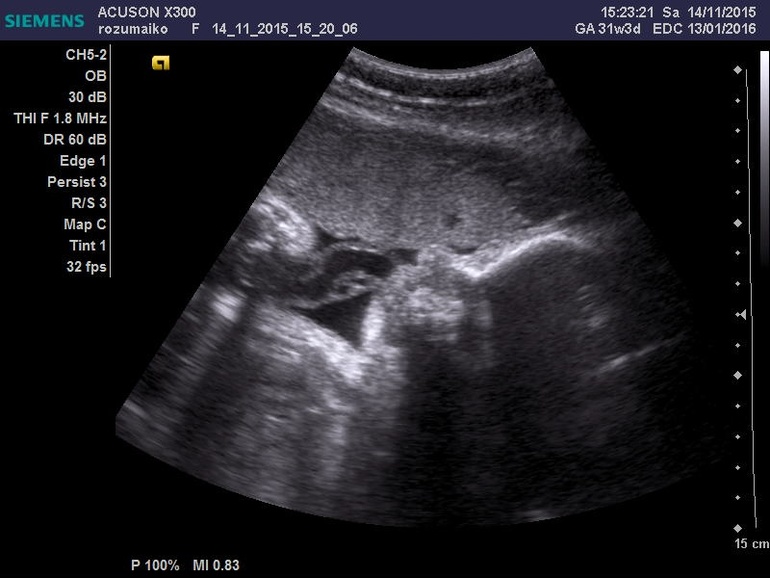

Малыш на 2 неделе опережает развитие на 31 неделе

УЗИ, КТГ, доплерШли на УЗИ боялись, что у нас гипоксия и у малыша остановилось развитие, а в результате оно опережает!

Срок: 31, 3 неделе

Гестационный возраст : 33, 2 неделе

Вес: 1915 гр.

ЧСС 141 уд/м.

плацента 33 мл, степень зрелости 2

обвития нет

околоплодные воды 301 мм (в повышенном количестве)

БПП 8 балов

Роди по месячным: 13.01.16

Роды по УЗИ: 31.12.15